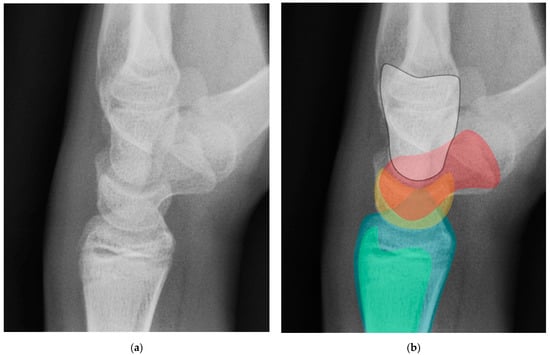

Figure 18. (a) Neutral lateral view wrist radiograph showing normal anatomy; (b) Radiograph overlay depicting its constituent anatomy; Green—ulna, Blue—radius, Yellow—lunate, Red—scaphoid, White—capitate.

Normal alignment of the carpus should always be assessed on neutral lateral view (Figure 18), as previously described [6]. In a normal wrist, a line can be drawn down the long axis of the radius that passes through the lunate, capitate, and metacarpals, with the radius cupping the lunate and the lunate cupping the capitate in a pillar-like fashion. Even with small amounts of projectional rotation, the biomechanical pillar along this line should remain intact. It is important to note that these intercarpal angles are only accurate on a “true” lateral view, when the pisiform is observed between the ventral surface of the capitate and distal pole of the scaphoid, ideally at the midpoint between these two structures.